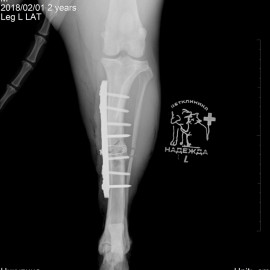

Наш пациент после автотравмы. Был проведен остеосинтез левой голени, в ходе которого была установлена динамическая титановая пластина с винтами. Так же были наложены серкляжные швы из титановой проволоки. Состояние пациента хорошее. Лапой пользуется активно.

Снимок 3-4 после операции